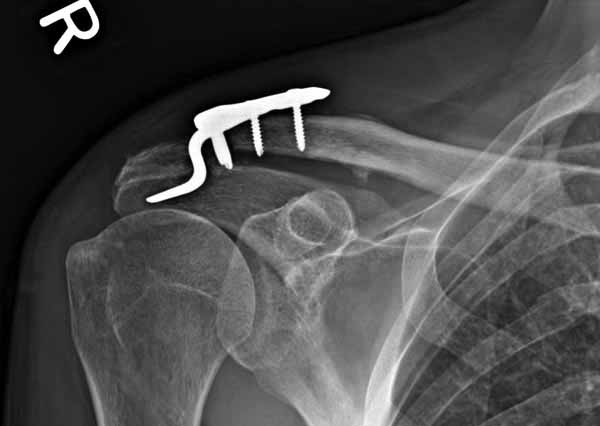

Из заданного вопроса в этом посте я понял, что разговор идет по поводу “методики применения ключичной пластины с крючком при акромиальных переломах”, т.е не ведется разговор “по поводу лечения косых переломов ключицы”.

Если так, тогда Юрий прав, методов лечения акромиона пластинами нельзя было найти. Обычно изобретали из реконструкционных пластин 2.7 или 2.4 мм толщиной. Такая фиксация адекватно удерживает перелом акромиона. Только недавно компания Acumed создала пластину для переломов акромиона, здесь линк: http://www.acumed.net/sites/default/files/literature/brochure-surgical-technique/CPS00-11-A.pdf.

По поводу пластины с крючком, Ваше заключение "не вижу препятствий для фиксации акромиального косого перелома ключицы для МОС использовать пластинку с крючком" вызывает сомнение.

Предназначенную для лечения повреждений связочного аппарата акромиально-ключичного сочленения пластину можно применить не при всех переломах акромиального конца ключицы. Потому что имплант рассчитан на интактную ключицу и не для переломов ключицы. Пластина короткая, не покрывает медиальный диафизарный фрагмент ключицы и за счет тракции стерноклеидомастоидеус такая фиксация прорвется через несколько дней.